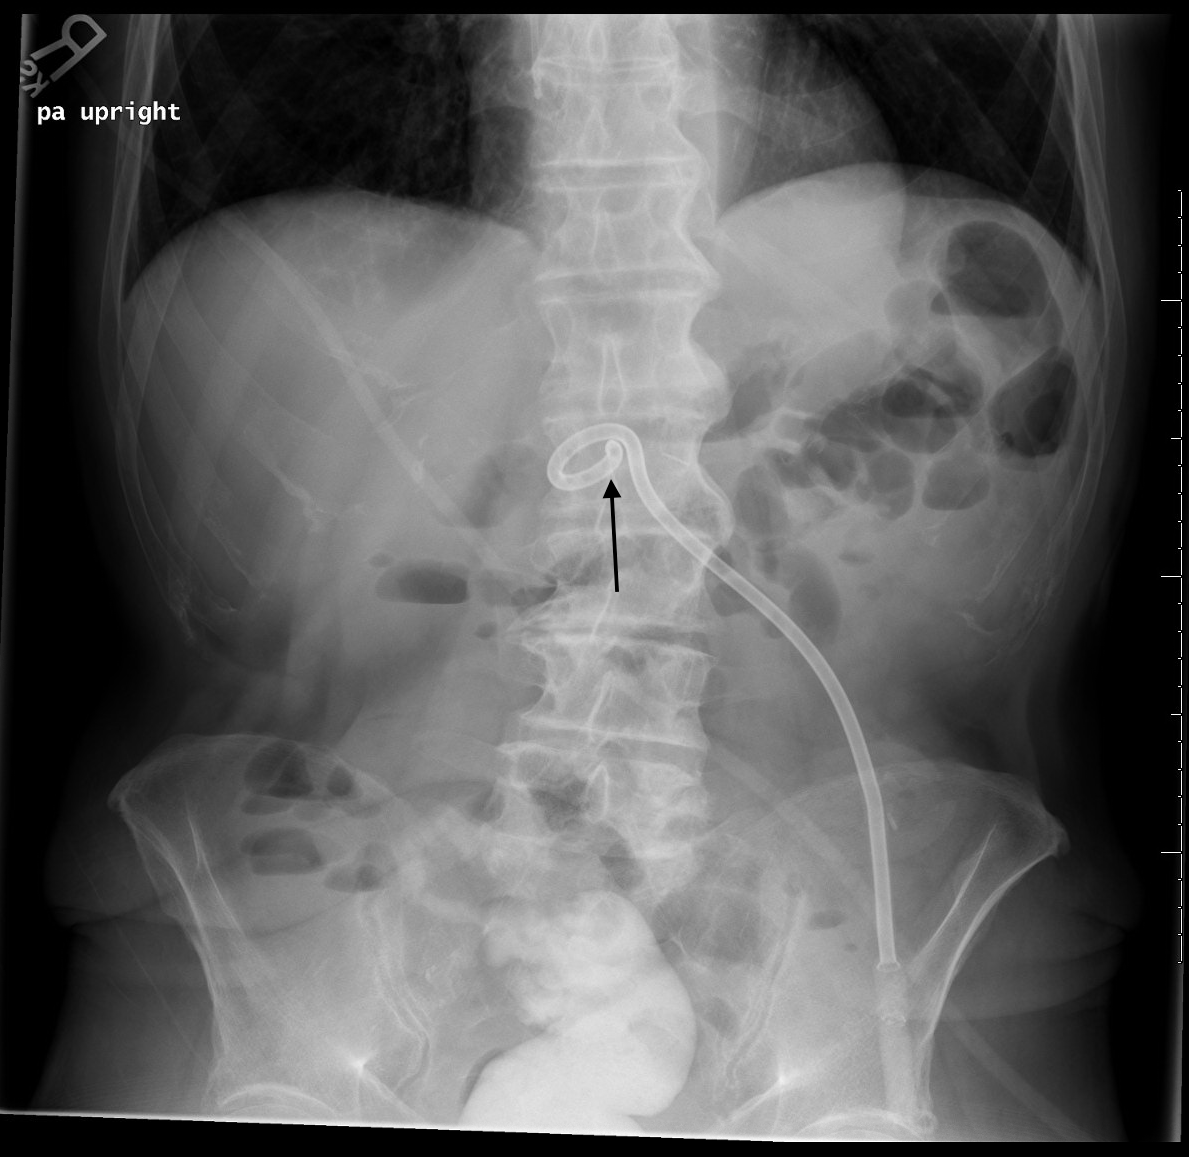

Upright abdominal Xray showing correct repositioning of PEG tube G-Tube Placement Check X Ray This topic will review the placement and routine care. Gastrostomy tubes may be placed endoscopically, surgically, or radiologically. Descend in the midline, following the path of the esophagus and avoiding the contours of the. The tube is used for feeding or drainage. Describe the anatomy of gastrostomy tube placement. A correctly placed nasogastric tube should 10: Classically, confirmation is achieved. G-Tube Placement Check X Ray.